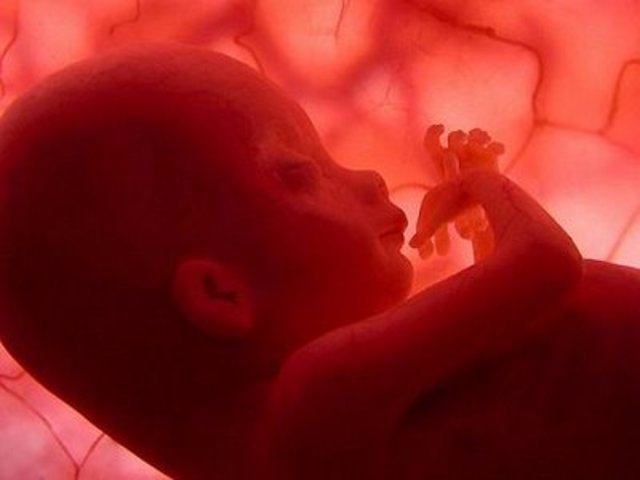

• Semana 8

Semana 8

Los ojos están desarrollados casi completamente. Los dedos se desarrollan y aparecen unidos por una membrana como en los anfibios. El corazón ha alcanzado su desarrollo total.

• Semana 9

Semana 9

La mayoría de los sistemas orgánicos han concluido su formación. Los dedos están completamente desarrollados. A partir de aquí el embrión se va a denominar feto.

• Semana 10

Semana 10

El cerebro crece rápidamente y alcanza el desarrollo completo. En la cara comienzan a apreciarse facciones humanas. Se han formado las cuerdas vocales y el feto es capaz de emitir sonidos. Aparecen las uñas. El feto muestra reflejos, su piel es sensible. Crece alcanzando 76 mm.